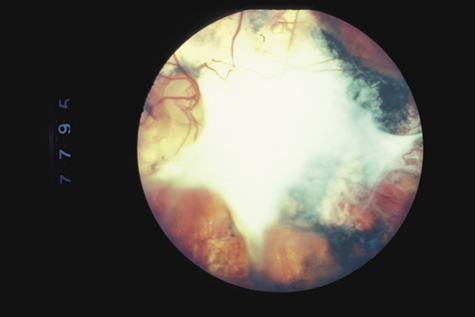

RETINAL DETACHMENT

Fig. 18. A typical traumatic retinal detachment. There is an inferotemporal retinal dialysis, a demarcation line, and no signs of proliferative vitreoretinopathy.